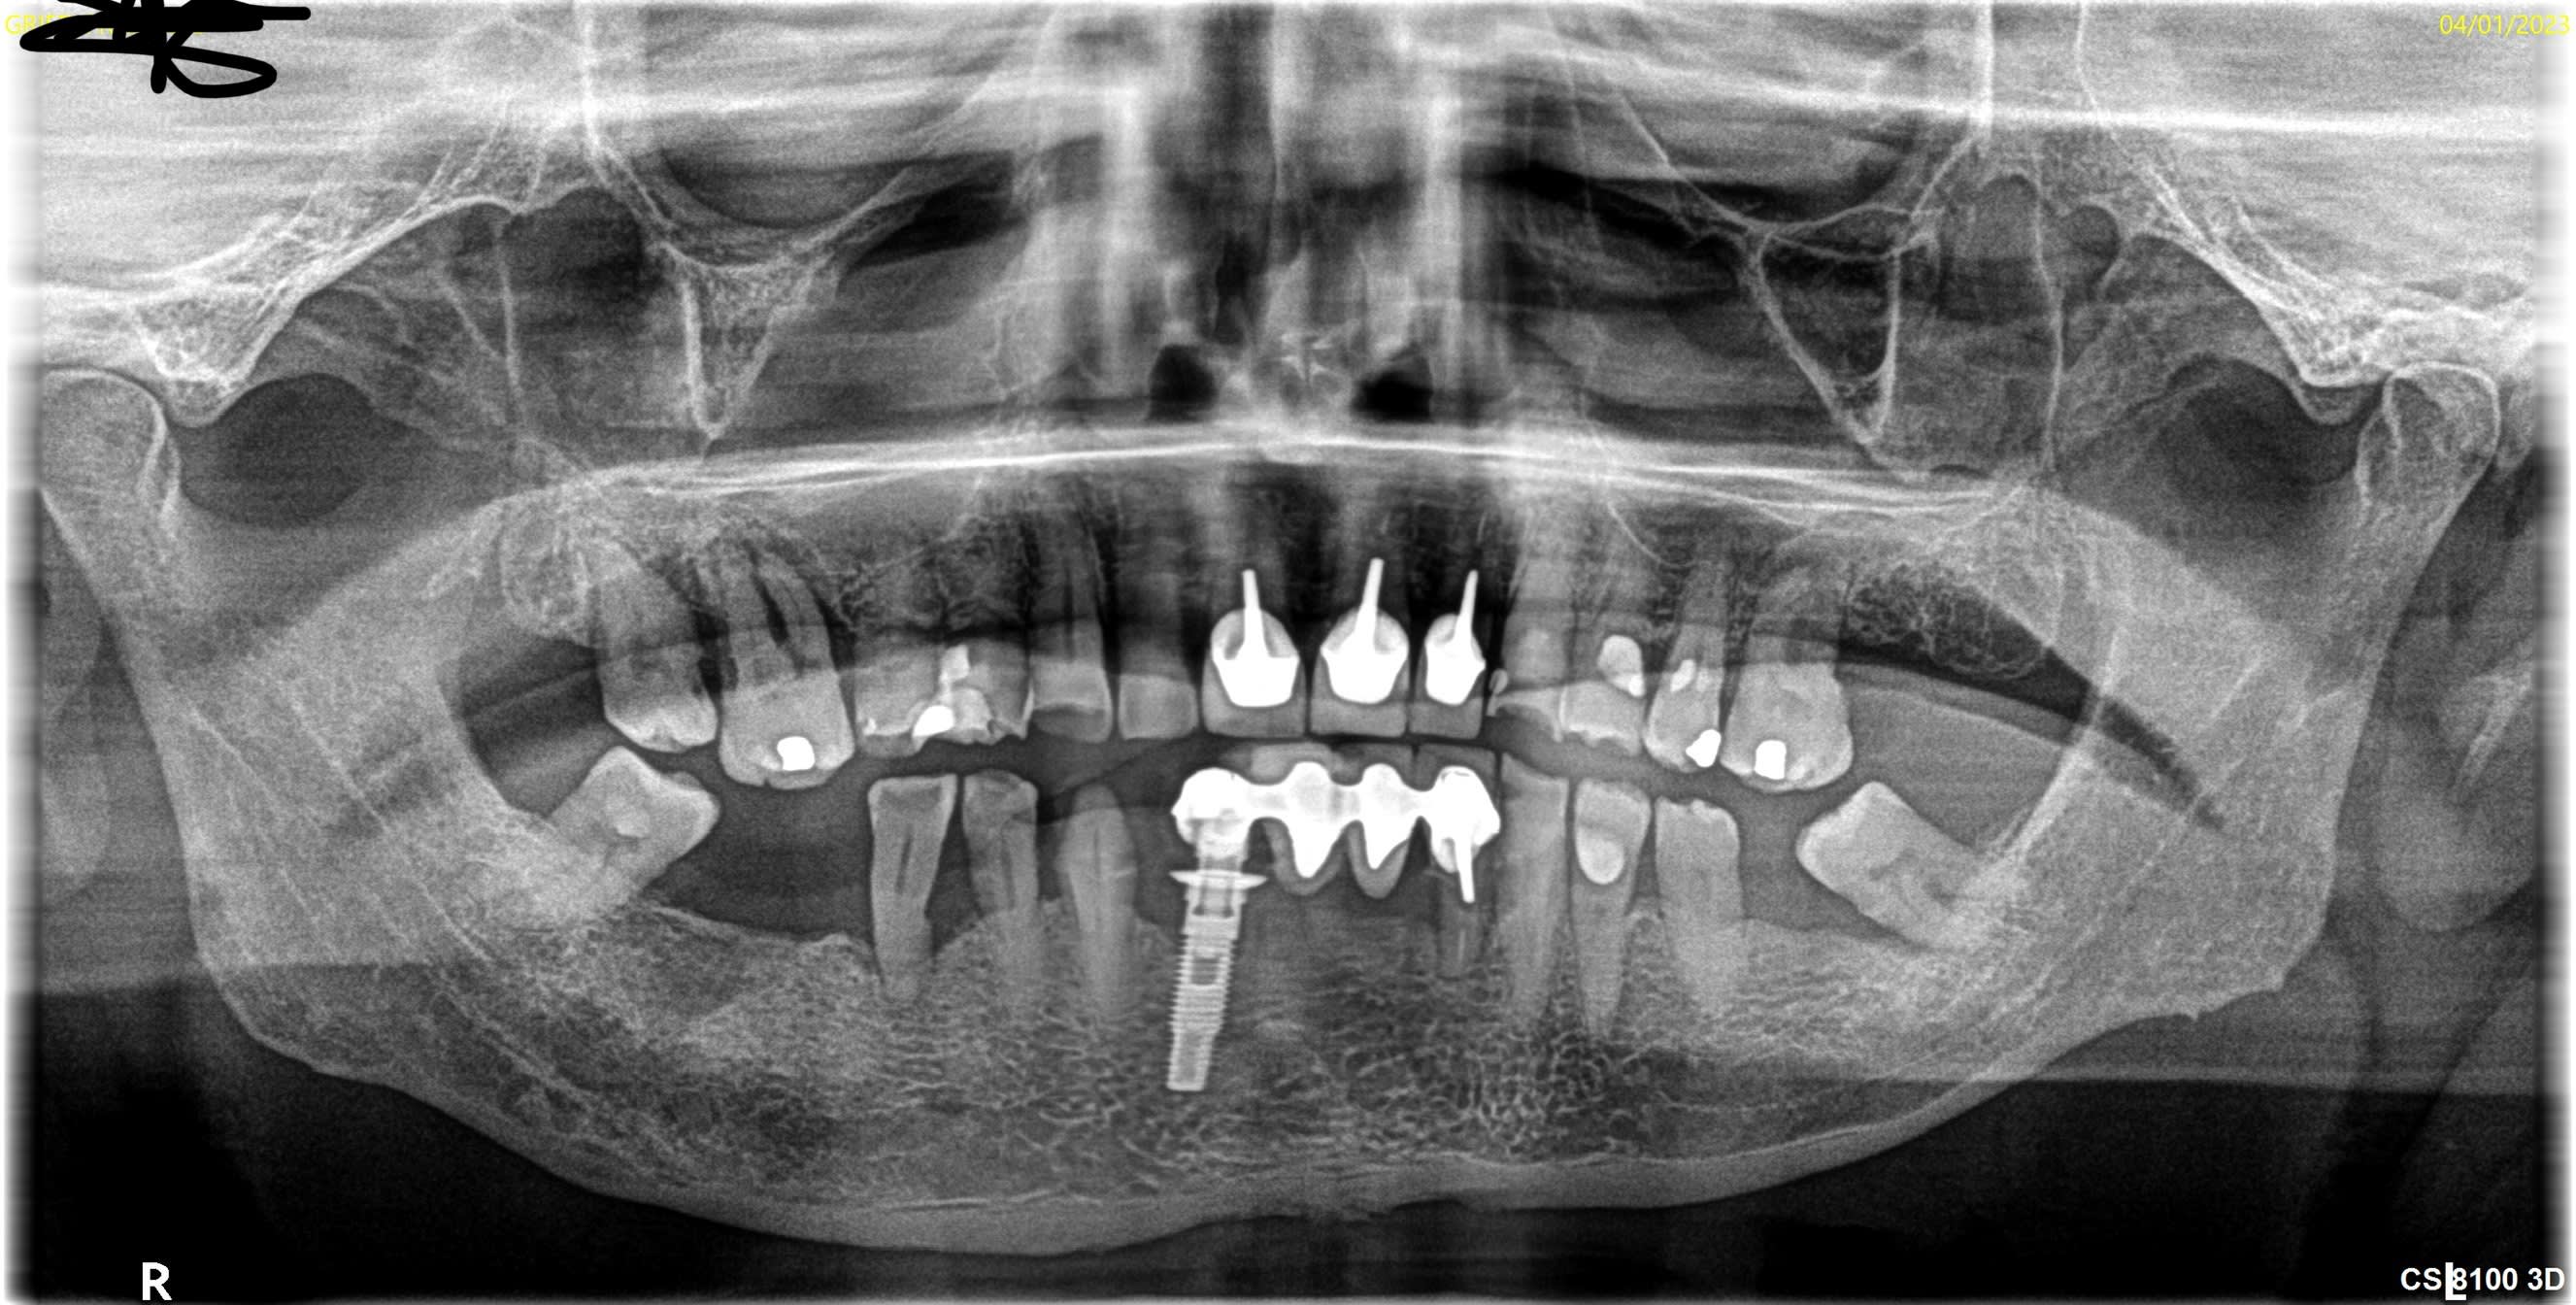

pourriez-vous m aider a identifier l'implant en 42.

Voici la rétro